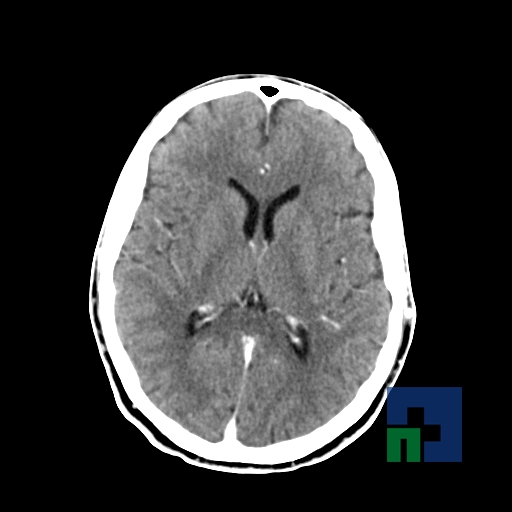

Examinare de rutină cerebrală, nativ și cu substanță de contrast (SDC) pentru diagnosticul:

- Accidentelor vasculare cerebrale ischemice sau hemoragice

În cazul traumatismelor cranio-cerebrale:

- Evaluarea deplasării liniei mediane

- Evaluarea cisternelor perimezencefalice

- Diagnosticul edemului cerebral, a contuziei cerebrale, a leziunilor axonale difuze edematoase/hemoragice, a dilacerării cerebrale, a hematomului intraparenchimatos posttraumatic, a hematoamelor subdurale/extradurale (acute, subacute, cronice), a hemoragiei intraventriculare, a hemoragiei subarahnoidiene

- Diagnosticul traumatismelor de bază de craniu

- Diagnosticul herniilor cerebrale

- Diagnosticul fracturilor: